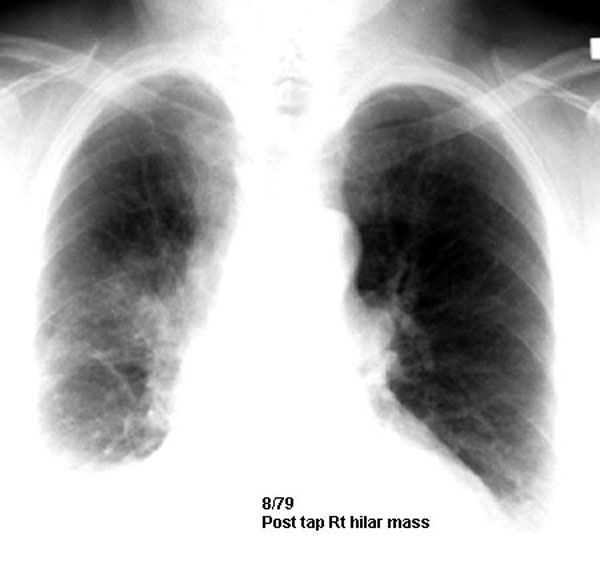

Post-tap film showing hilar mass